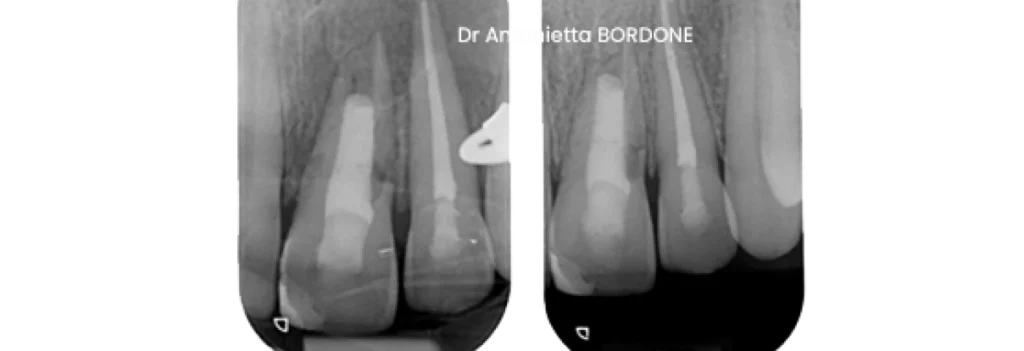

Exemple de revascularisation :

Bénéfices attendus

Les parois radiculaires s’épaississent. La racine gagne en longueur. L’ancrage osseux s’améliore avec le temps. La résistance aux fractures augmente. Le pronostic fonctionnel progresse nettement.

Points d’attention